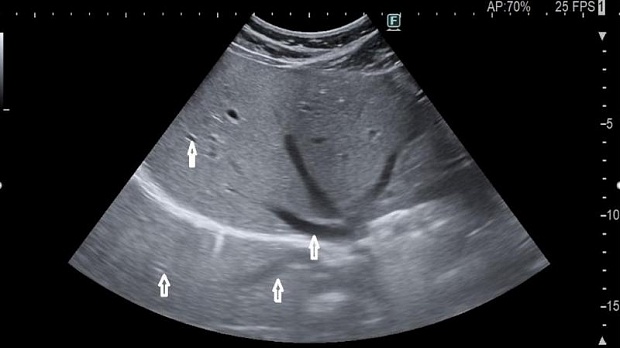

Акустическое усиление – противоположно акустическому затемнению и происходит дистальнее объекта с низким затуханием, например, полость, заполненная жидкостью. При этом УЗ-волна проходит быстрее через изучаемый объект, чем вокруг него, в результате чего происходит «псевдоусиление» сигнала, хотя правильнее было бы сказать, что на этом участке происходит менее выраженное (в сравнении с окружающими тканями) ослабление (затухание) сигнала.

Рис.6 Анэхогенное поражение печени с тонкой гиперэхогенной стенкой с дистальным акустическим усилением, что подтверждает жидкостное содержимое и диагноз простой кисты печени.